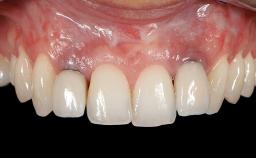

GBR and Soft-Tissue Augmentation Following Explantation to Rehabilitate a Soft- and Hard-Tissue Defect

It is sometimes necessary to remove and replace compromised implants. This case is a clear example of the need for multiple steps to achieve an optimal therapeutic result for patients with non-salvageable implants. It illustrates how the lost soft and hard tissues were rebuilt in a sequence that improved the healing of the hard tissues and assured their long-term stability. The 35-year-old healthy patient presented with clinical attachment loss on the proximal and lingual surfaces of the natural dentition. Some gingival recession was present on natural teeth, particularly in the posterior sextants (S1, S3, S4, and S6).